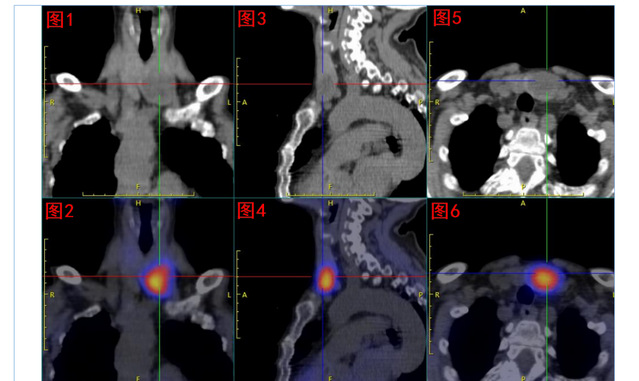

核医学科双时相甲状旁腺核素SPECT/CT显像发现:甲状腺左叶下极处显像剂异常浓聚,考虑为功能亢进甲状旁腺组织;但是该组织主体位于甲状腺左叶内,非甲状旁腺常见部位,遂反馈给吕荣主任医师团队,建议进一步行甲状旁腺及甲状腺超声检查。

99mTc-MIBI甲状旁腺SPECT/CT融合显像图:图1+2冠状位、图3+4矢状位、图5+6横断位,提示功能亢进甲状旁腺组织(十字线交叉处)。随后的超声提示:双侧甲状旁腺区多断面超声扫查未见明显异常占位性病变;双侧甲状腺结节,其中左侧叶内一枚33mm×19mm低回声、边缘光滑、内无强回声结节。颈部B超图:A、B(纵切面)分别显示甲状腺左叶、甲状腺右叶;左叶内一低回声结节。